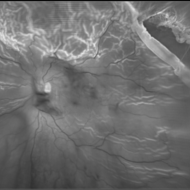

Total Rhegmatogenous retinal detachment with lattice degeneration & Vitreous haemorrhage

Jul 31 2023 by Harsh Vardhan Singh, MS

72-year male presented PVD induced total retinal detachment with vitreous hemorrhage

Photographer: Dr Harsh Vardhan Singh, AIIMS, Guwahati

Imaging device: Zeiss Clarus 700

Condition/keywords: chronic retinal detachment, hemorrhage, rrd